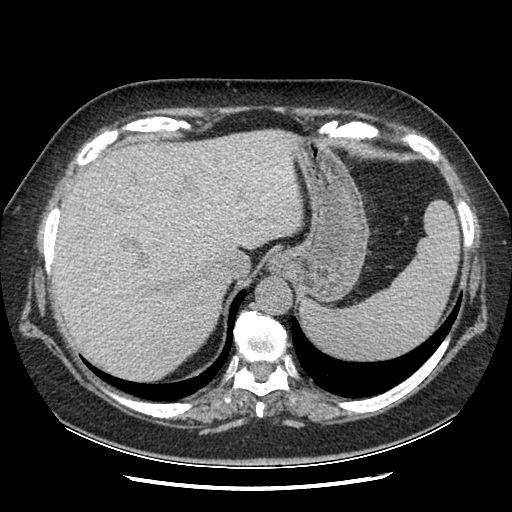

Original VENOUS CT scan

Full window (WL 1023.5, WW 4095 β†’ Low βˆ’1024, High +3071)

Actual HU range: [-160.0, 240.0]